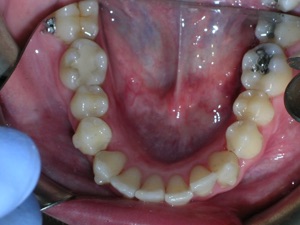

This case was of a young lady who desperately wanted Invisalign, but had been told it was not possible. There was not one, but two teeth that had come in toward the roof of the mouth.

Here are some progress photos.